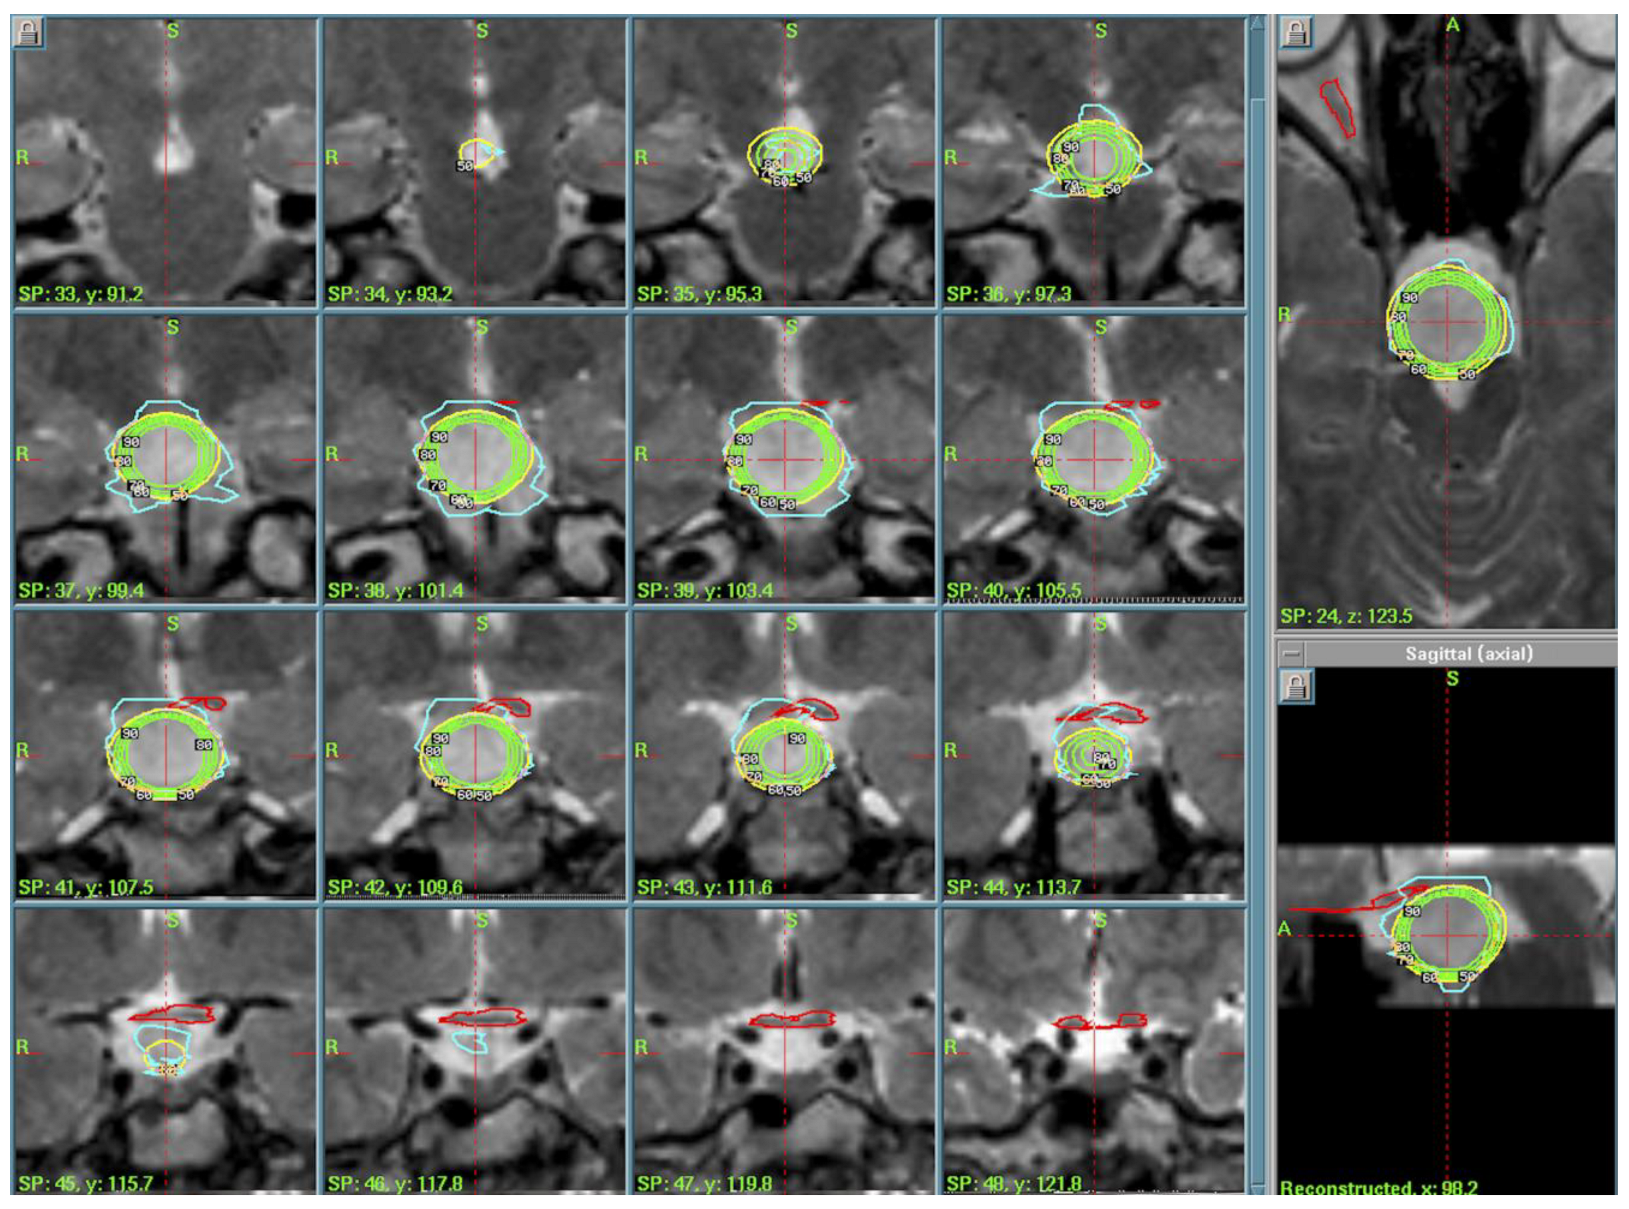

3.1. Hypothalamic Hamartoma (n = 3)

| 1. | Hypothalamic Hamartoma | PI of 50%, PD of 11 Gy, MD of 22 Gy | 2004–2020 |

| 2. | Hypothalamic Hamartoma | PI of 50%, PD of 13.5 Gy, MD of 27 Gy | 2005–2010 |

| 3. | Hypothalamic Hamartoma | PI of 50%, PD of 13 Gy, MD of 26 Gy | 2009–2019 |